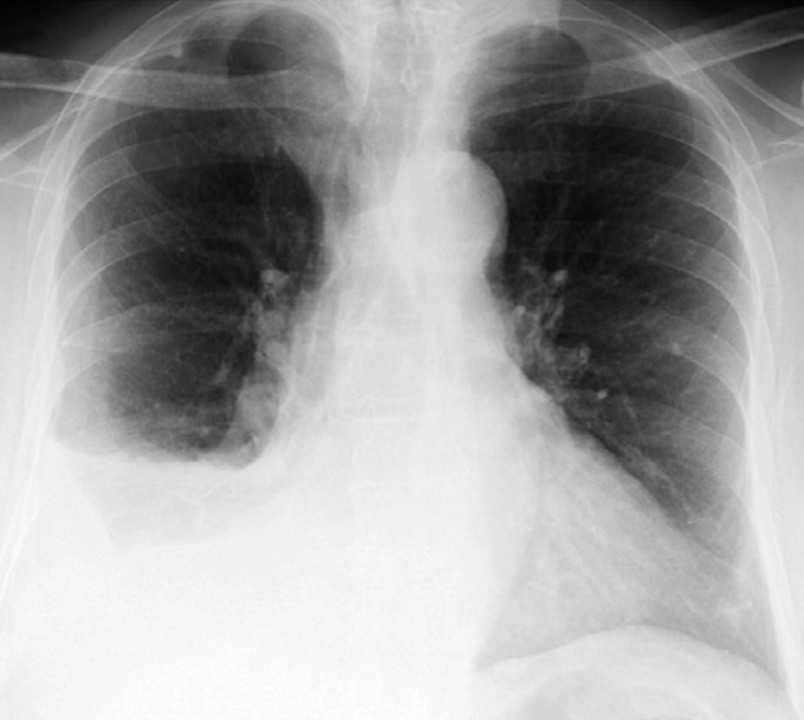

Рентген-снимок легких больного с плевритом и жидкостью в правой плевральной полости. Фото: Respiratory medicine case reports / Open-i (CC BY-NC-ND 3.0)